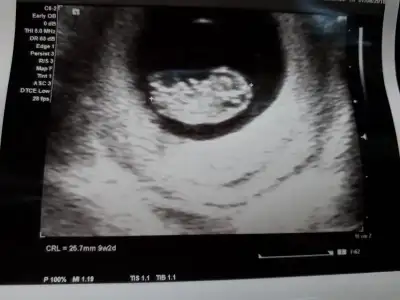

Bebeğimi gördükk. :) 9+4'üm bugün. Haftasıyla uyumlu, kalbi gümbür gümbür atıyor eskisine göre maşallah. :) 20 gün önce hiçbir şey belli olmuyorken şimdi elleri, kolları, kafası... Doktor 2 hafta sonra 2'li test için çağırdı.